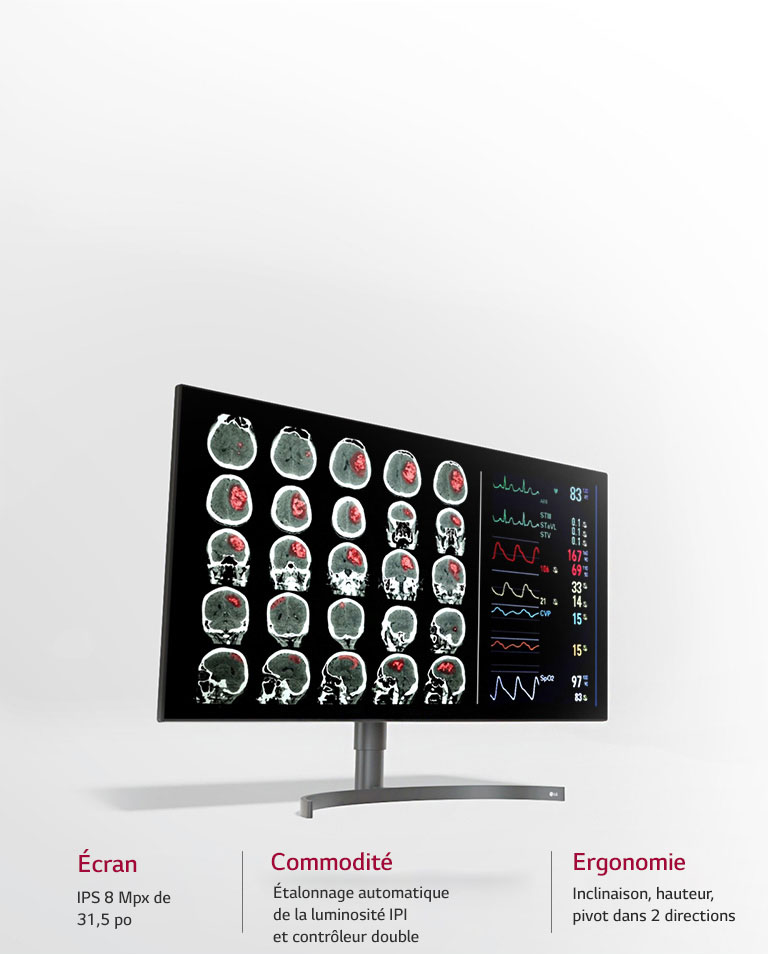

Qualité d’image optimisée pour la révision des diagnostics

Pour augmenter l’efficacité et la commodité

Key Feature

- Écran IPS 8 Mpx de 31,5 po

- Mode multi résolution

- IPI / Contrôleur double

- Étalonnage automatique de la luminosité

- Mode pathologie clinique

- Conception ergonomique